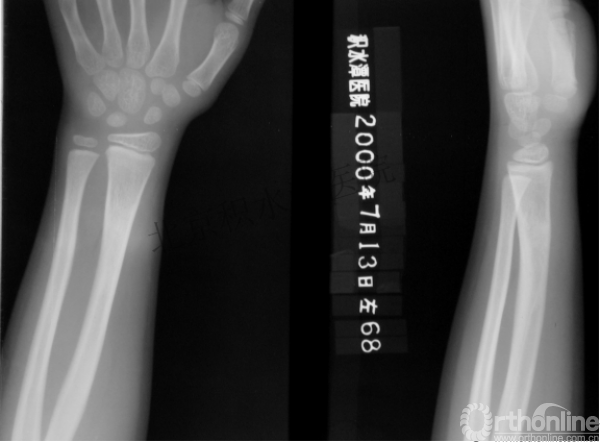

病例分享四

女孩、8岁,桡骨远端骨折

原始损伤

伤后1个月

伤后14个月